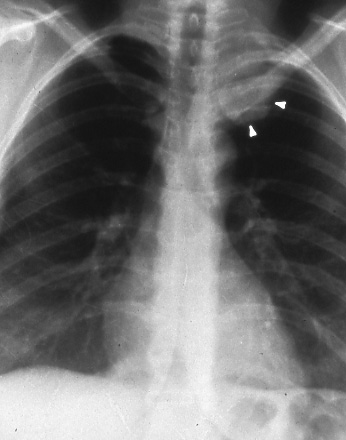

Fig. 49b: Magnetic resonance imaging of the chest showing tumor (T) and vertebrae (v). Arrow points to tumor extension directly into the neural foramen, T4 N0 M0, stage IIIB12.